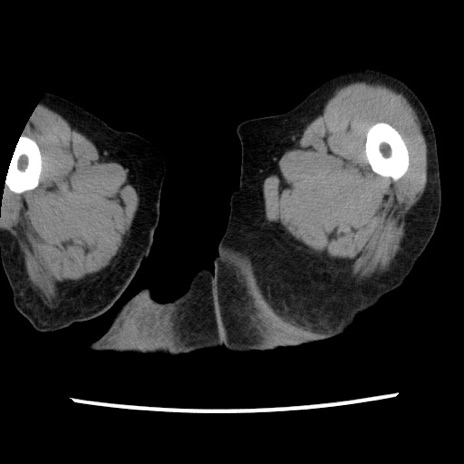

症例1(横断像)

症例

【症例】80歳代女性

【主訴】腹痛

【現病歴】8時間前から腹痛あり来院。

【既往歴】糖尿病、脂質異常症、子宮体癌にて子宮全摘術

【身体所見】意識清明・会話良好だが腹痛で苦悶様、全腹部にわたって反跳痛と圧痛あり

【データ】WBC 13600、CRP 0.14、LDH 224、CK 90